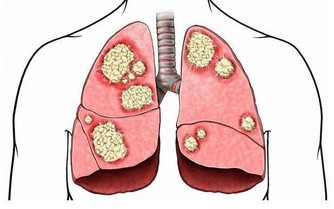

慢性支氣管炎是氣管、支氣管黏膜及周圍組織的慢性非特異性炎症。臨床以咳嗽、咳痰為主要症狀,每年發病持續3個月,連續2年或2年以上。

慢性支氣管炎,是一種不會致命的比較頑固的慢性疾病,給患者帶了I諸多的不便和痛苦。雖然不致命,但如果患者日常生活這一些習慣行為做的不好,也是可能會導致癌變的發生的。

患慢性氣管炎或者支氣管炎時,身體會出現咳嗽、痰等症狀。如果病情嚴重,還會發展成肺功能衰竭甚至癌變,危及生命安全。那麼,對於患有慢性氣管炎的患者,應該採取哪些措施來緩解這種疾病呢?